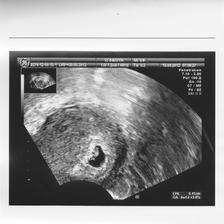

Tehu..3.pokus

autorahoj moje...no neviem,pregnyl už na 9DPO bol snehobiely,i tak sa bojím,lebo tu niekomu ukázal pozitívny testík a potom negatívny..ach jaj,sú to nervy...ja idem v utorok na krv.pocity??- malinko nejaká zmena v prsiach,ale taká malá,že ani neviem,čo,presne,...,žravosť,..a teraz som skoro zaspala za volantom...

ja neviem,je to veľmi slabé...mama test ,dúfam,že nie chybový...v utorok budem vedieť viacej... 🙂